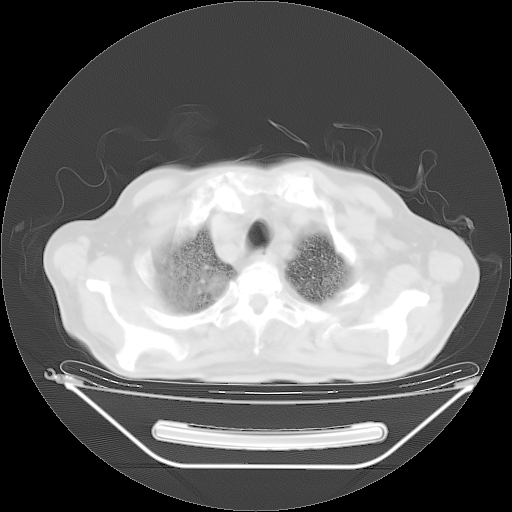

今天复查肺部CT,发现双肺广泛磨玻璃样改变。所以我把3月19日和5月9日相隔50天的肺部CT上传。请大家会诊。

5月9日肺部CT(在4月27日齐鲁医院肺部CT描述部分肺组织磨玻璃样改变,12天后肺组织广泛磨玻璃样改变)

大致读了系列胸部CT:纵隔窗无明显异常,肺窗:从4、27至今:主要是双肺中下野外带可见毛玻璃样改变,目前处于急性肺泡炎阶段,至于原因考虑1、结替组织或胶原血管性疾病所致?2、恶性疾病如恶组在肺部所致的表现或细支气管肺泡癌?3、药物或其它原因如肺蛋白沉着症所致肺泡炎目前不太可能?总之,明天就去请我院的呼吸科、感染科、血液科和临免专家会诊哈。